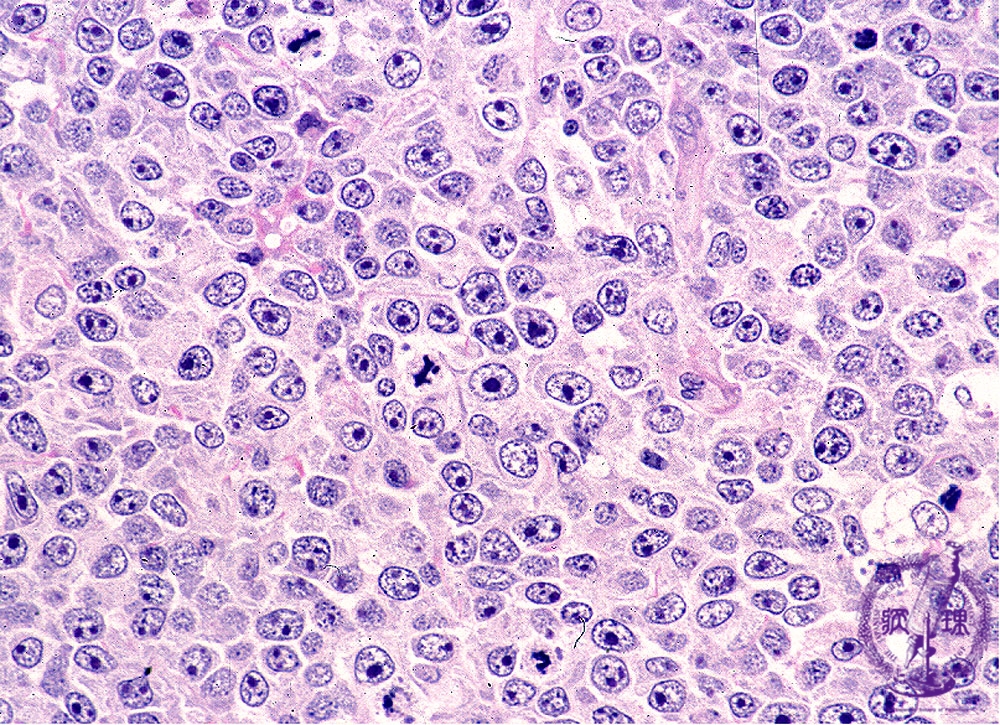

びまん性大細胞型 B 細胞リンパ腫 (DLBCL) は、非ホジキンリンパ腫のサブタイプです。多くの人は第一選択の治療法に反応しますが、多くの人は難治性または再発の DLBCL を経験します。